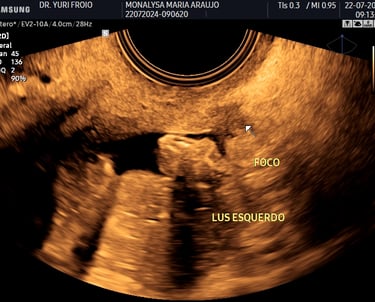

Ecografia Vascular com Doppler

A ecografia vascular com Doppler avalia o fluxo sanguíneo em artérias e veias identificando obstruções, varizes e tromboses. É um exame não invasivo, essencial para diagnóstico e acompanhamento de doenças vasculares. Proporciona informações detalhadas para uma abordagem clínica precisa.